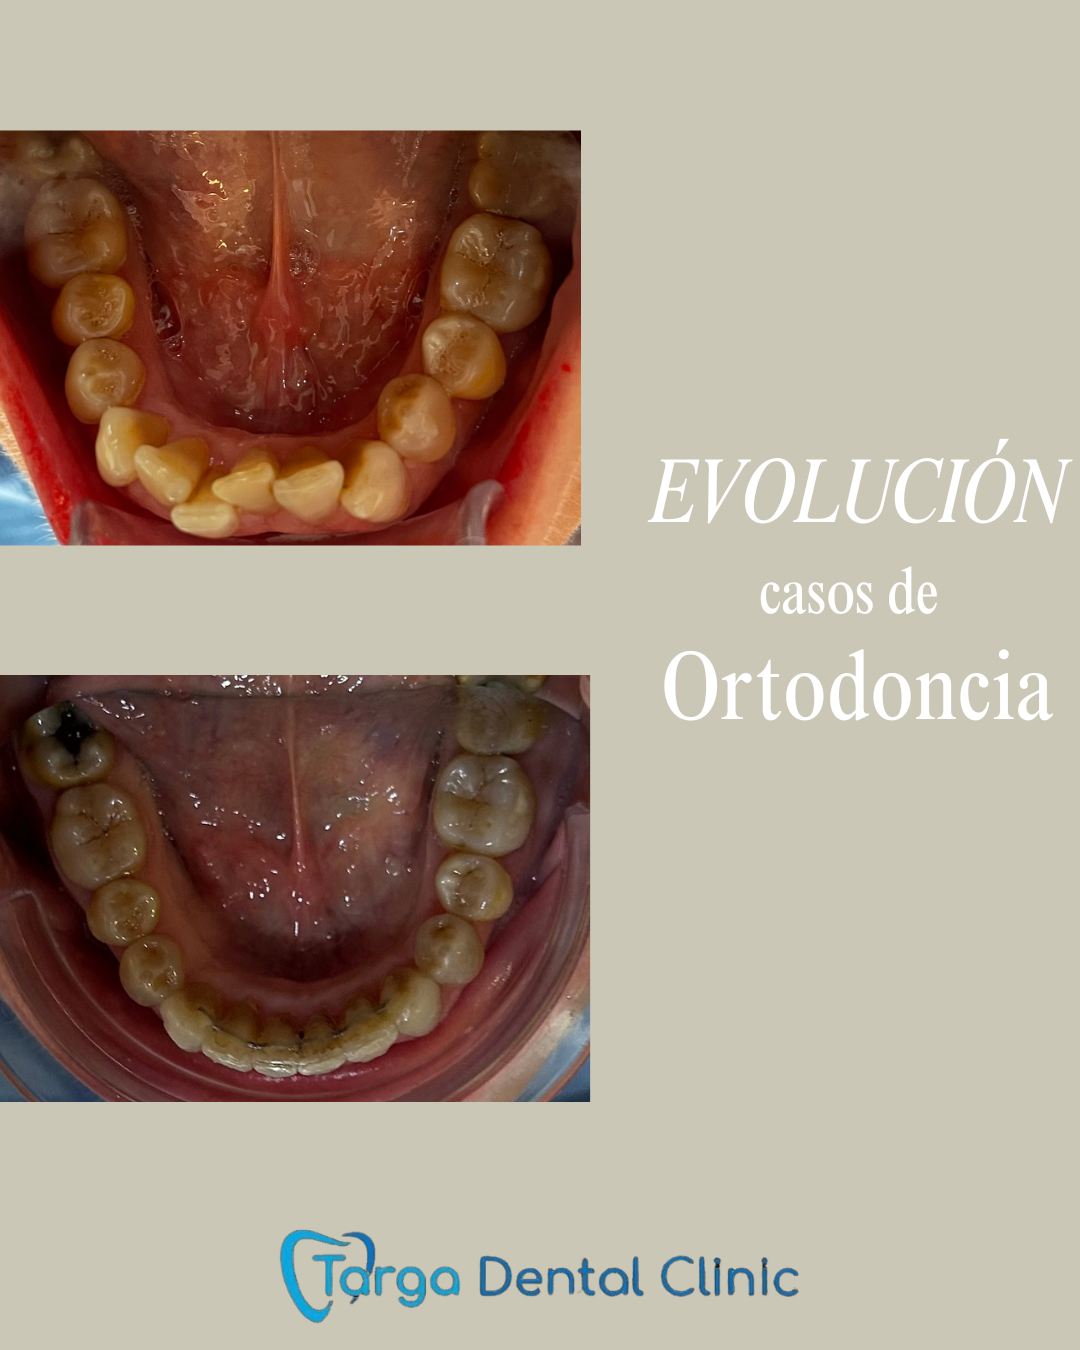

Ortodoncia y Odontopediatría

Ofrecemos tanto ortodoncia invisible con alineadores como ortodoncia fija con brackets.

Evaluamos cada caso y te recomendamos el más adecuado para ti. También ortodoncia para los más pequeños y los pacientes en crecimiento.

Tratamientos realizados en nuestra clínica